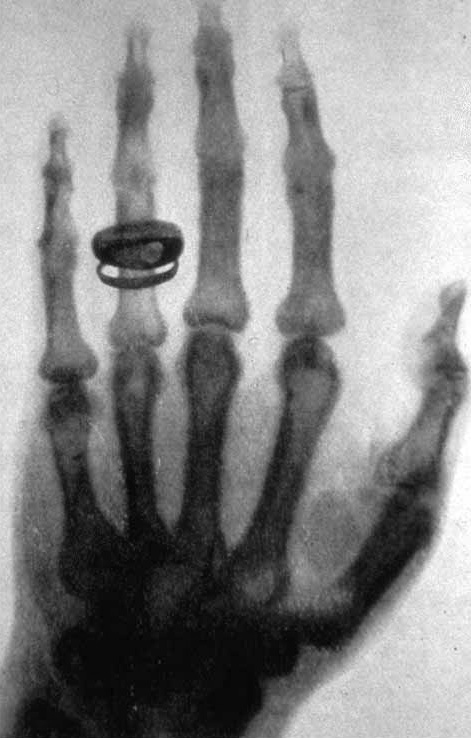

En 1895, découverte des rayons X